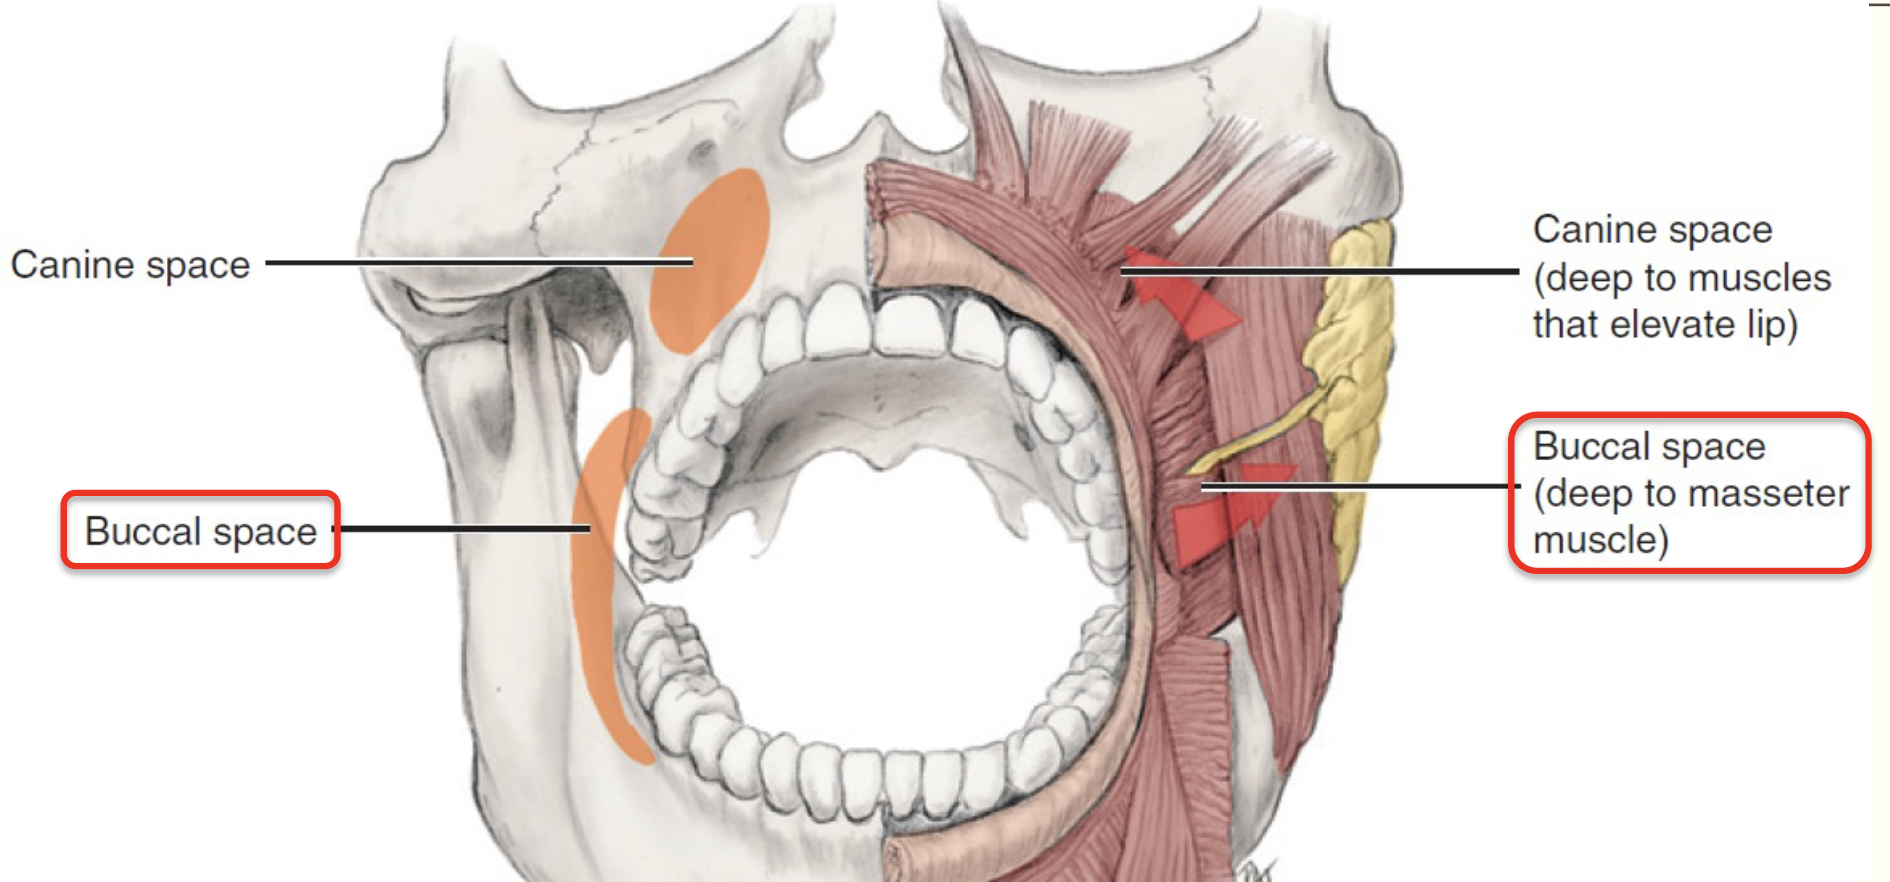

Canine space (Maxilla)

Buccal space

- Buccal fat pad

- Parotid duct

- Facial a.